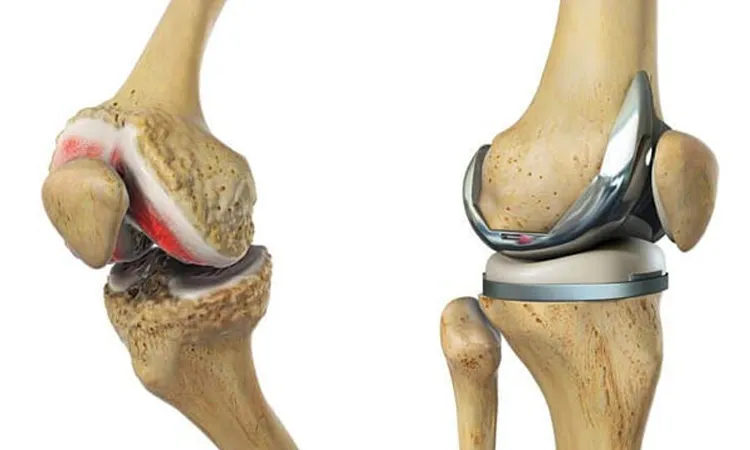

درمان های جراحی آرتروز

چالشهای درمان جراحی آرتروز شامل موارد متعددی است که بر موفقیت و نتیجه نهایی عمل تأثیر میگذارد. یکی از مهمترین چالشها، انتخاب زمان مناسب برای جراحی است؛ جراحی زودهنگام ممکن است منجر به نیاز به جراحیهای مجدد شود و جراحی دیرهنگام نیز ممکن است باعث آسیب گستردهتر به بافتهای اطراف شود.

علاوه بر این، خطرات ناشی از جراحی مانند عفونت، خونریزی، لخته شدن خون و مشکلات بیهوشی بخصوص در بیماران مسن یا دارای بیماریهای زمینهای وجود دارد. همچنین، فرآیند بهبودی و بازتوانی پس از جراحی ممکن است طولانی و نیازمند همکاری کامل بیمار باشد که در برخی موارد به دلیل سن بالا، مشکلات حرکتی یا عدم پیروی از توصیههای پزشکی با مشکل مواجه میشود.

در صورتی که درمانهای غیر جراحی نتوانند به بهبود وضعیت کمک کنند یا علائم شدید و ناتوان کننده باشند، ممکن است جراحی نیاز باشد

جراحی آرتروسکوپی

آرتروسکوپی یک روش جراحی کم تهاجمی بهترین درمان آرتروز است که با استفاده از دوربین و ابزارهای خاص، مشکلات داخلی مفصل مانند پاره شدن غضروف یا آسیب به منیسک را درمان می کند.

جراحی تعویض مفصل

تعویض مفصل شامل برداشتن مفصل آسیب دیده و جایگزینی آن با یک مفصل مصنوعی. این روش معمولاً برای مفاصل بزرگ مانند زانو یا ران انجام میشود.

جراحی فیوژن مفصل

فیوژن مفصل نوعی عمل جراحی برای جوش دادن دو یا چند استخوان به یکدیگر برای تثبیت مفصل و کاهش درد است که در بهترین درمان آرتروز انجام می شود.